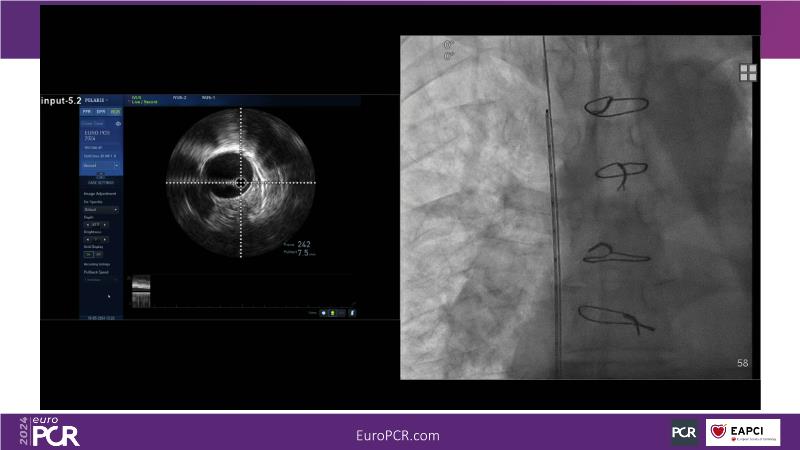

Watch this session to gain comprehensive insights into the use, safety, and efficacy of heterotopic tricuspid valves. Learn to identify ideal candidates with severe tricuspid regurgitation, understand key procedural factors for successful implantation, and receive tips on valve systems and anatomy. The session also includes a recorded TricValve case, discusses the current status of transcatheter tricuspid valve therapies, and explores the placement of heterotopic tricuspid valves in the guidelines.